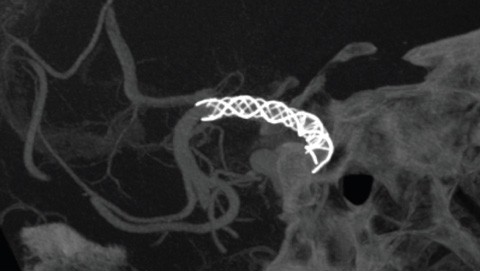

VasoCT IA ist ein Erfassungsverfahren, das ein hochauflösendes XperCT mit Kontrastmittelinjektion kombiniert, um die Visualisierung von endovaskulären Implantaten, Flow Divertern und anderen Implantaten sowie der Gefäßmorphologie bis auf Perforatorebene zu verbessern. Es wird zunehmend für die Nachuntersuchung von mit Flow Diverter Implantaten behandelten Aneurysmen verwendet, um die Positionierung des Implantats zu überprüfen.

Moderne Devices zur Behandlung zerebraler Aneurysmen sind teilweise nur sehr schwierig erkennbar, wodurch sich die Dauer solcher Eingriffe erheblich verlängern kann. Deshalb ist eine exzellente 2D- und 3D-Bildgebung wichtiger denn je, denn sie erleichtert die Entscheidungsfindung wie auch die Implantat-Platzierung und ermöglicht gleichzeitig eine effiziente Kontrolle der Strahlendosis.

Moderne Devices sind sehr klein und teilweise nur schwer in der Bildgebung darzustellen. Dies erschwert natürlich die Navigation und die genaue Positionierung der Devices. Gleichzeitig sollen arterielle Dissektionen und Spasmen vermieden und die Strahlendosis reduziert werden.